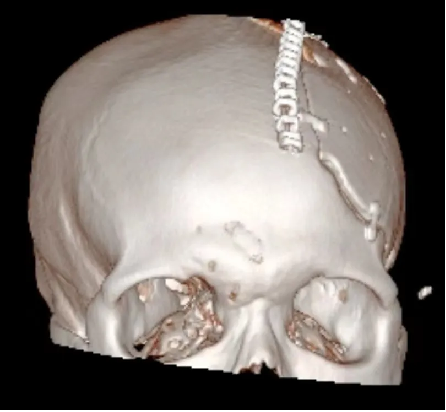

患者汪某,男性,66歲,因重症顱腦(nǎo)損傷,多發肋骨(gǔ)骨折,血氣胸,鎖骨骨折辦理入院緊急手術,醫院神經外科專家團隊為患者行開顱血腫清除+大骨瓣減壓術。手術順利,術後(hòu)恢複滿意。專家團隊將患者手術去除的顱骨骨瓣進行了清洗、滅菌後低(dī)溫冰凍儲存。

患者術後滿三個月(yuè)再次返院進(jìn)行顱骨缺損(sǔn)修補術,經過完善術前檢查、全(quán)科討論、做好充分手術(shù)準備後,武(wǔ)寧縣總醫院人民醫院院區神(shén)經外科團隊成功為患者完成(chéng)自體顱骨修補術(shù)。

術後: